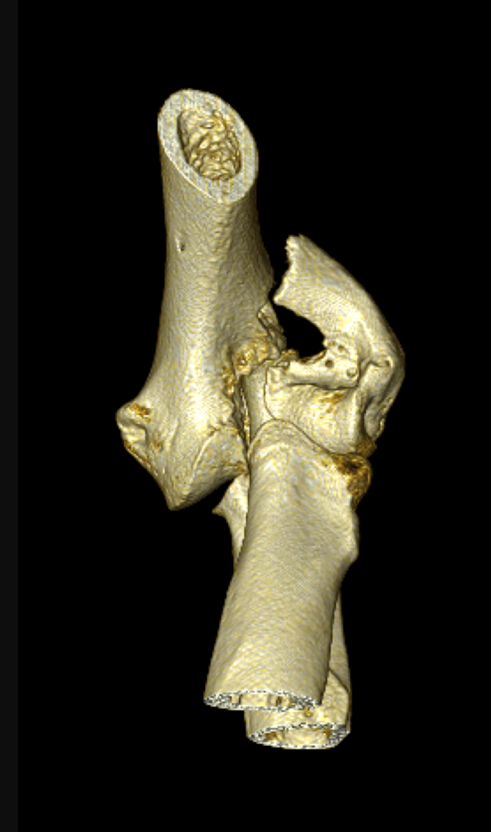

Fig. 2: Rechter elleboog vertoont een fissuur zonder verplaatsing intercondylair. In de linker elleboog zijn beide condylen van elkaar losgeslagen.

In een 3 d reconstructie (Fig.3.) is het totaalbeeld nog duidelijker en zie je de verplaatsing van de laterale humerus condyl en de fractuur lijn in de epicondylaire kam lateraal.

Fig. 3: